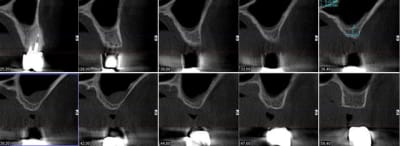

pour illustrer cette utilisation du bioactys, voici un cas (ce matin, mise en focntion des implants à 7 mois post_op)

la chir est résumée en vidéo ici:

C'était un peu limite non pour la pose immédiate, faible hauteur osseuse initiale.

pour la pose immédiate, çà dépend aussi du type d'implant utilisé...ici c'est des superline dentium...;-)

ils ont vraiment une super stab primaire, et leur design est parfait pour les zones sous sinusienne...entre autre....parce que pour l'instant, mis à part le manque d'un repère visible sur le préhenseur de la position de l'hex antirotationnel, j'ai pas encore trouvé de défaut au système...